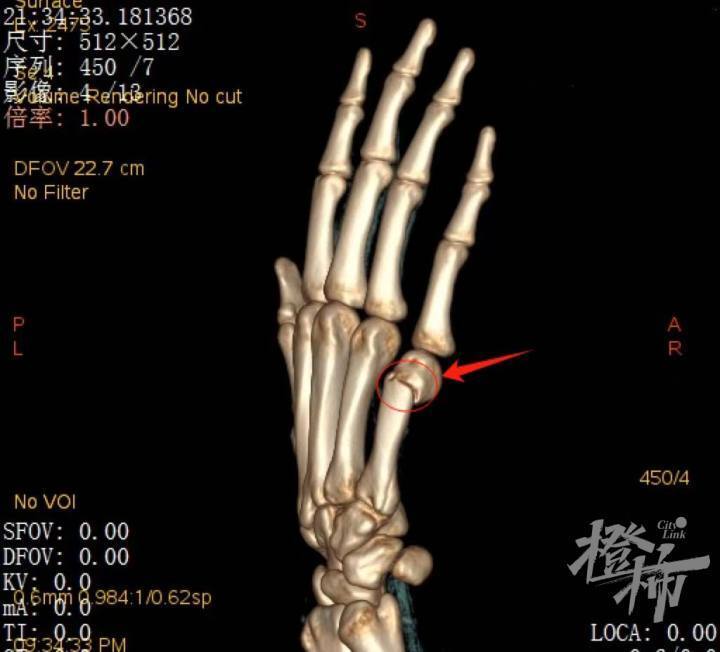

某boxers骨折患者ct三维重建图像 医院供图拳击手骨折,它并不是拳击

病因:这种骨折最常见的是人们用握紧的拳头猛击坚硬的表面(或另一个人

于握拳击打损伤所致,同样的损伤机制,第4掌骨颈部骨折,也称boxer骨折

发于第4,5掌骨,因为拳击手比赛时,容易发生此类损伤,故称为拳击手骨折

boxers 骨折(来源:radiopaedia)(来源:radiopaedia)第 1 掌骨基档哪

boxers knuckl拳击手指节拳击手骨折是发生于掌骨的骨折,最常见的是